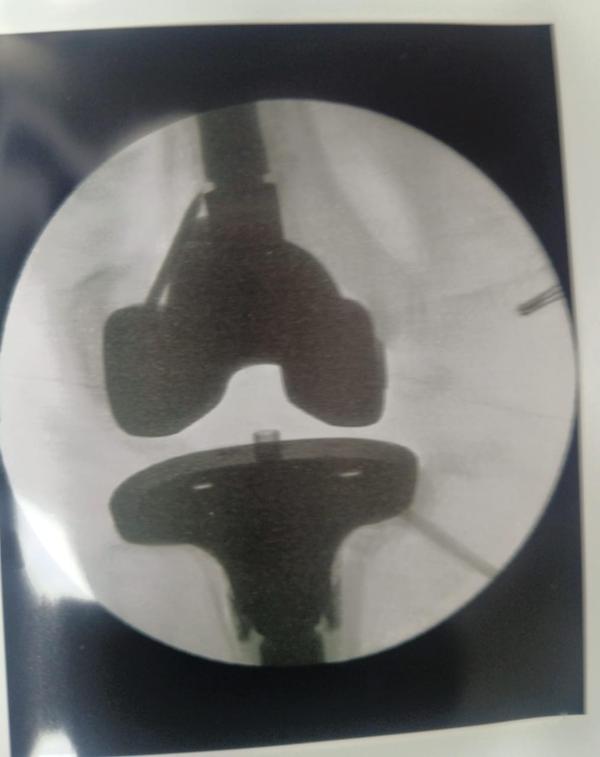

Revision Hip And Knee Replacement

Dr Randive has 25 years experience in Revision Knee and Revison Hip Replacement surgeries. It took him more than 25 years of training hard work and thousands of surgeries to achieve excellence in Revision Knee and Hip Surgeries. He has successfully achieved this milestone through extensive training.